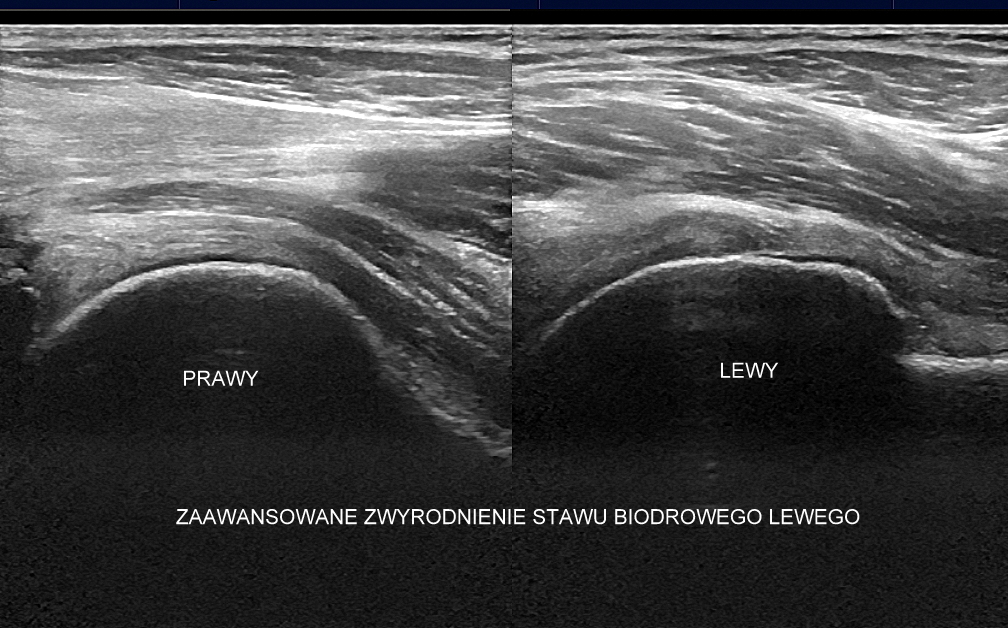

USG stawu biodrowego

USG ma istotne choć ograniczone znaczenie w diagnostyce stawu biodrowego. U niemowląt używane jest przede wszystkim w ramach profilaktyki preluksacyjnej, a u dzieci starszych w celu oceny urazów sportowych i zapaleń (np. odczynowych). U dorosłych z kolei USG okolicy biodra wykorzystywane jest przy wykrywaniu stanów zapalnych, wysięku w stawie biodrowym, zmian zwyrodnieniowych, niektórych urazów w samym stawie (np. urazy obrąbka stawowego), a także patologii w sąsiedztwie, takich jak tendonopatie, zapalenia kaletek, zespół bólowy okolicy krętarza większego, uszkodzenia i naderwania mięśni okolicy biodra, krocza oraz pachwiny, uszkodzenie Morela-Lavallée’a, przeskakujące pasmo-biodrowo-piszczelowe, przepukliny pachwinowe i udowe, neuropatie, limfadenopatie, tętniaki, a także inne.